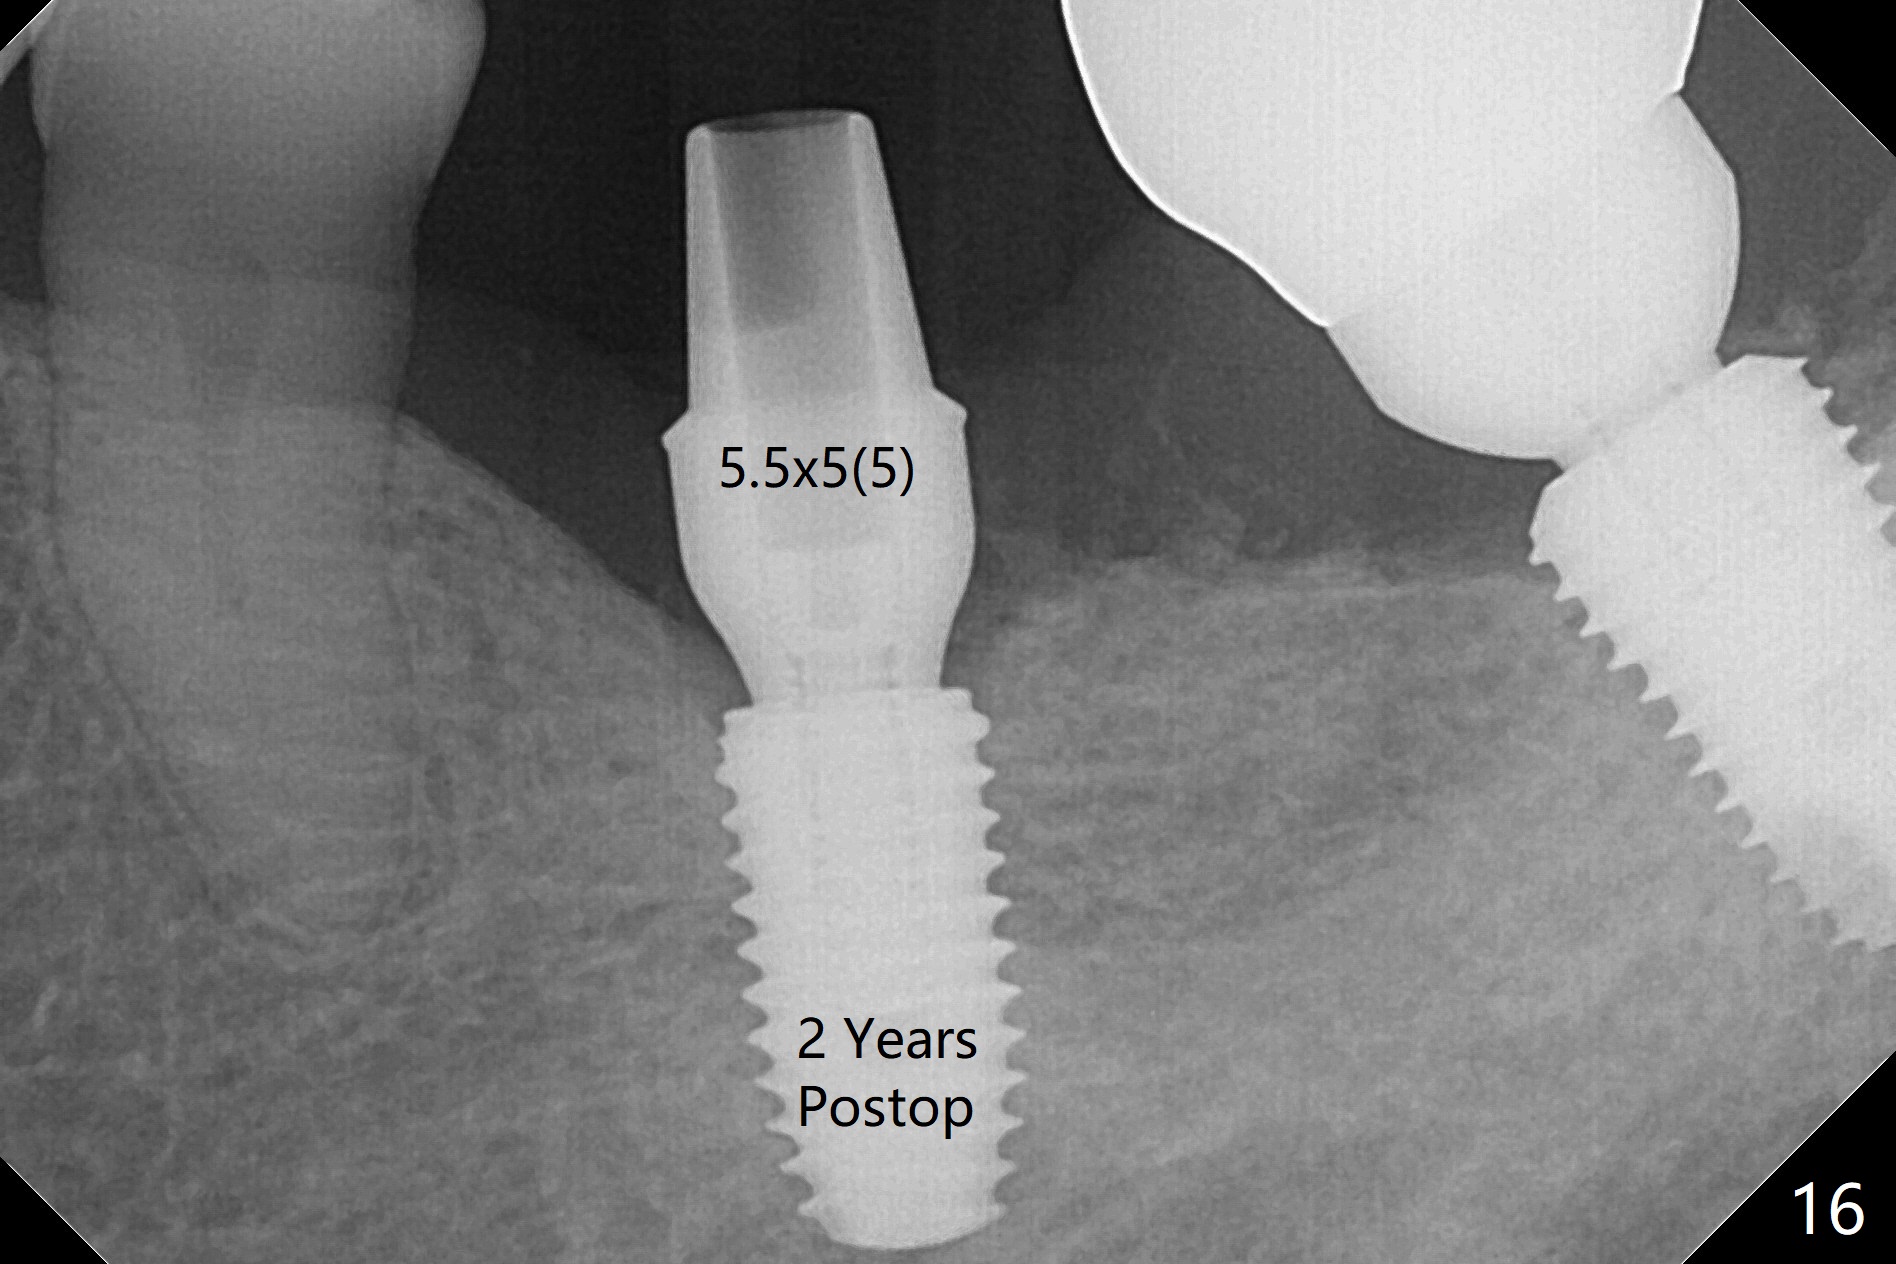

Probably due to severe infection at #19, pain control is difficult. Osteotomy has to be stopped 1.5 mm short of the design. PA taken with a 4.5x10 mm dummy implant does not show the Inferior Alveolar Canal (Fig.1), whereas CT does (Fig.2). With 6 mm clearance, block anesthesia is administered. A 5x10 mm definitive implant is placed with ease (Fig.3). The buccal bony defect is repaired by allograft (Fig.3,4 *), while the soft one by 3 pieces of PRF membrane (Fig.5). The latter is fixed in place by applying setting acrylic as an immediate provisional (Fig.6 P) over the wound, around the abutment (A) and locking into the undercut of the neighboring tooth/implant crown. The patient feels great postop. The gingiva is healthy around the provisional 8 days postop (Fig.7). The patient remains asymptomatic with the healthier gingiva surrounding the simplified provisional 22 days postop, as compared to 8 days postop (Fig.8). The socket heals when the simplified provisional is removed 1.5 months postop (Fig.9-12). The bone graft (Fig.11 ^) seems to have become a part of the regenerated gingiva. The abutment has been dislodged for 2 week (Fig.14 (3 months postop). The bone graft, albeit decreased, is 2 mm subgingival (red dashed line). There is bone distal to the implant 11 months postop (Fig.15 *). There is no bone loss 2 years postop; the UF abutment is completely seated (Fig.16).